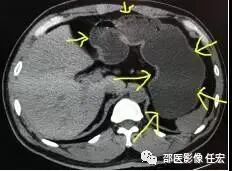

如上图1:黄色箭头指的就是胃,这是一个没有喝水,没有充盈好的胃,我们可以看到箭头指的胃壁是明显厚的,正常的胃壁也是厚的,但是如果里面隐藏长着东西,刚好胃壁这里有个小胃癌,那就没办法诊断了,就会导致漏诊。

再看看图2:这个患者胃肠道准备做得很好,我们可以看到一样是黄色箭头里指的胃,里面装的都是水,胃壁被填充成薄薄的一层了,如果长东西胃壁异常增厚,那么就可以一目了然了。